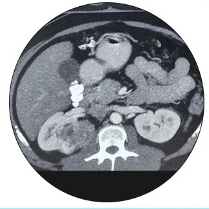

Young patient presenting with incidentally detected right-side renal tumor on sonography.

CT scan revealed an aggressive tumor extending toward the hilum, (The neck of the kidney where blood supply enters.)

Tumor close to the hilum, posed challenges for its removal while preserving the healthy part of the kidney.